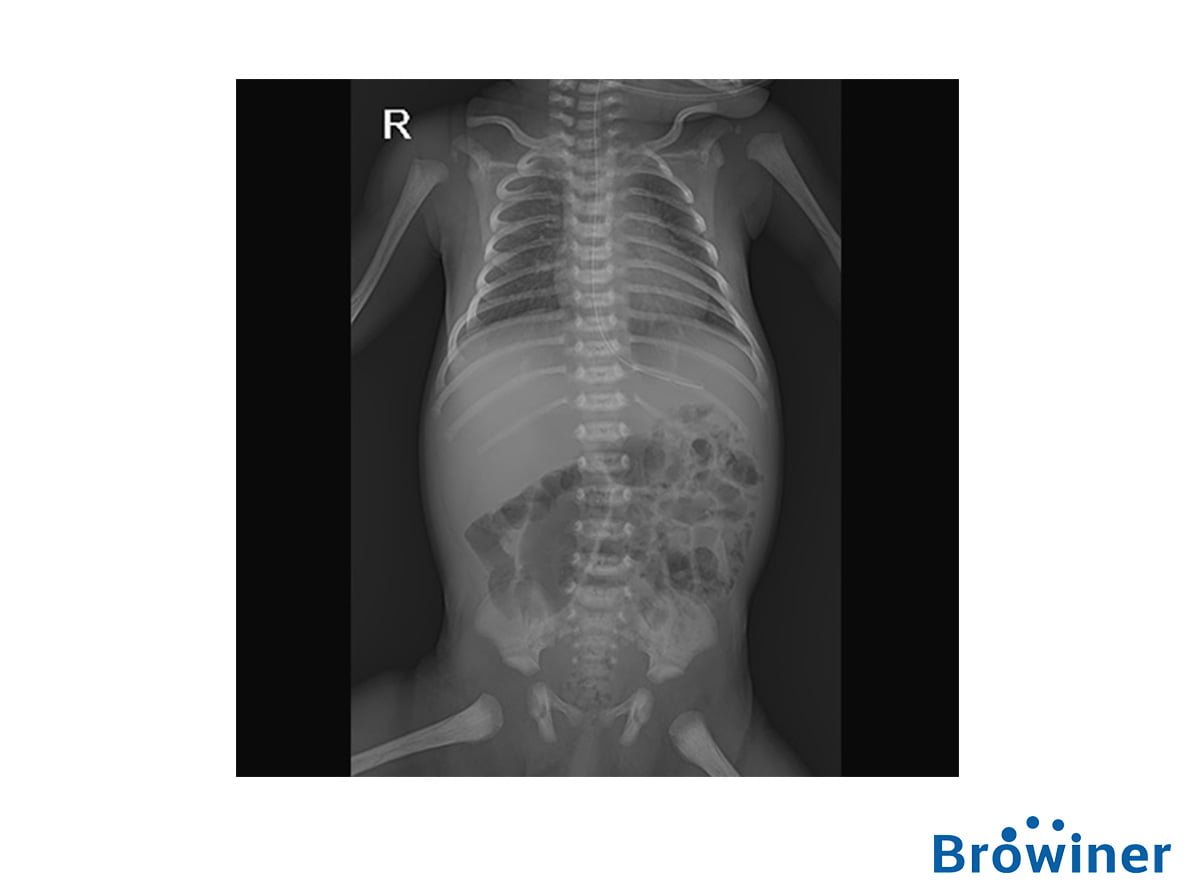

El Emer/Neo DR es un equipo de rayos X altamente integrado que ahorra tiempo a los doctores y enfermeras en situaciones de emergencias.

Con un cuerpo delgado y un diseño compacto, Emer/Neo DR se puede transportar y usar fácilmente en un lugar complicado y estrecho.

Con una baja dosis de radiación y la compatibilidad con la incubadora como sus principales características, Emer/Neo DR se puede usar dentro de la incubadora infantil, lo que brinda una mayor atención integral para los bebés.